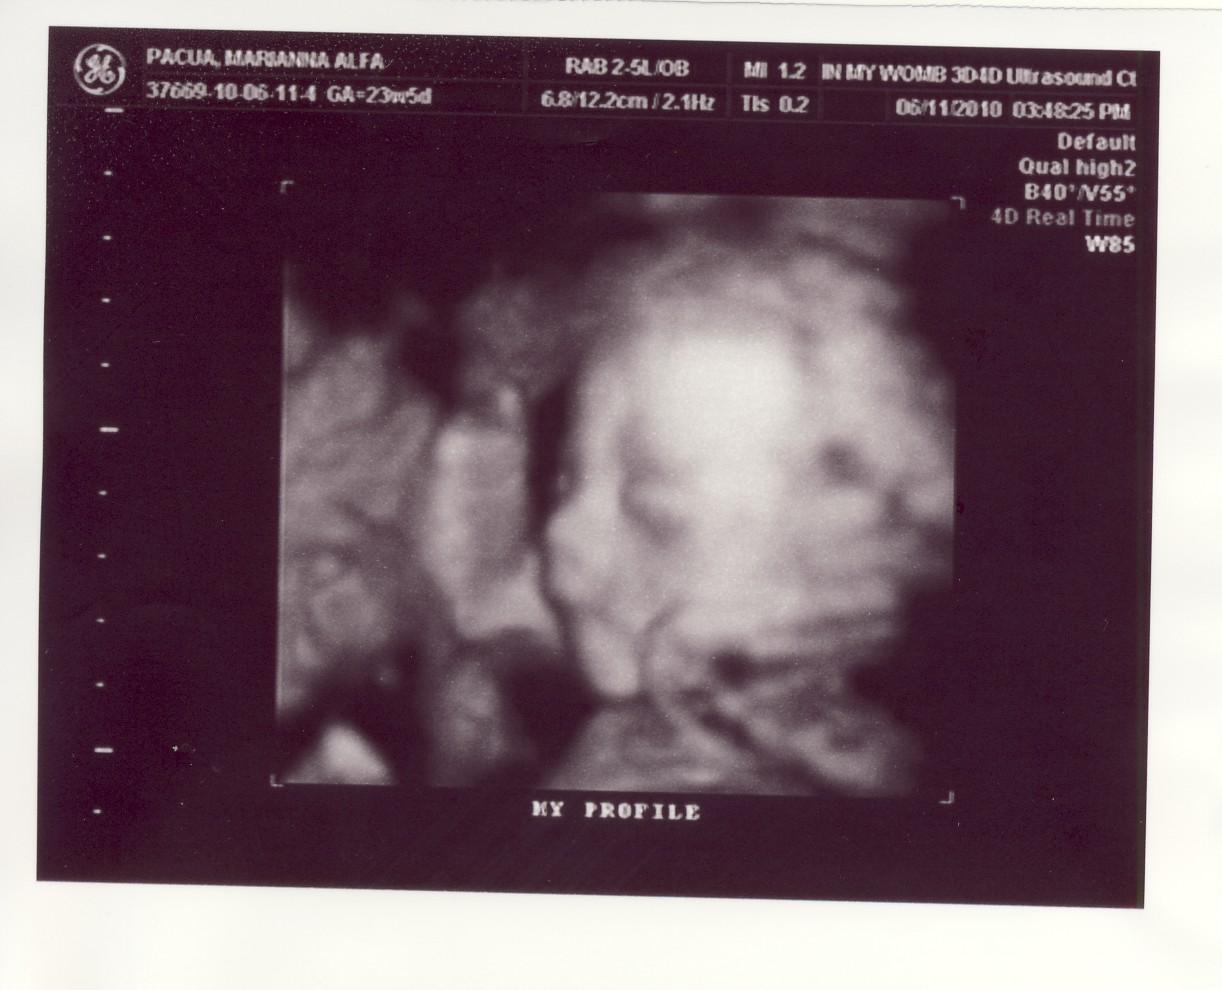

It was a fun scan, and the doctor even showed us the baby in 3D, which was absolutely, absolutely magical :-) She threw in a free profile pic in our envelope even if we got only the basic 2d package! Thanks so much!!